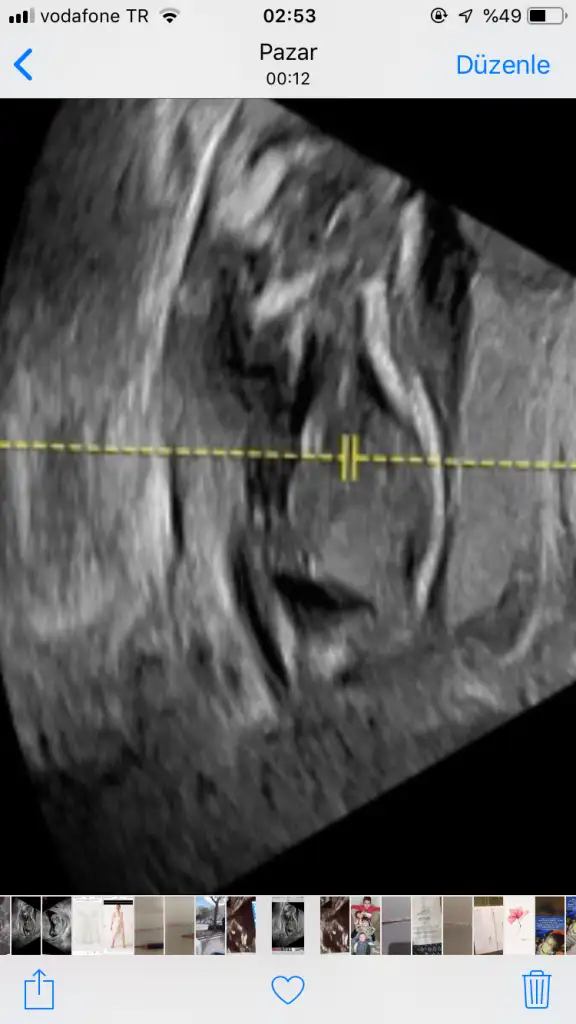

Önceki usgde 15 sanırım orda pipi değil pitis vardıBenim 16da böleydi benek secdede asla kıpırdamadı uğraşmadıda doktor alttan baktı ama 1 kere baktı kız dedine foto ne bişi düzgün vermedi bunu vermiş muayene 10dk bulmamıştır yani o sebeple 20bekliyorum yinede

Evet onda şunu verdi, buna bakış bende kız diyorumÖnceki usgde 15 sanırım orda pipi değil pitis vardı

Bende de işte 16. Haftada erkek dedi şimdi 20 de kesin demedi ama ayrıntılıda kesinleşir dedi. Hadi bakalım kızsa Selinim geliyor ☺Canım benim 16haftada büyük kızımda profdu doktorum yüzde doksan erken d dedi ismini bile koyduk, sonra 20de kesin kız olduğunu öğrendik bende video vardı burdan edindiğim bilgilere göre geçen videosunu açtım baktım büyük kızımın 16.haftasını gerçekten bacak arasınd çıkıntı vardı başbaşa erkek gibi gözüküyordu ozaman anladım neden erkek demiş 20.de o çıkıntı gitmişti, bazen klitoris 16da çıkıntı duruyor erkek sanıyorlar ben hep 20yi bekliyorum o sebeple